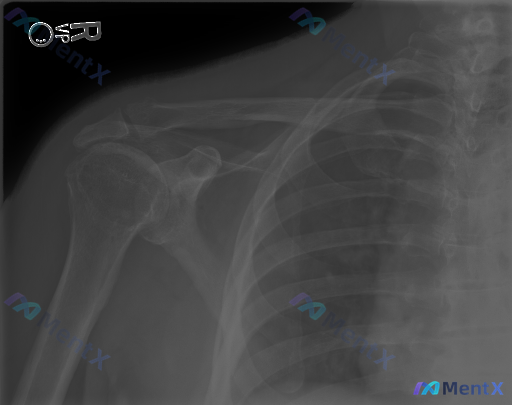

📷 右肩关节正位X光所见:

- 肱骨头、关节盂、锁骨远端、肩峰这些骨性结构都还好,没有明确的骨折线、脱位或半脱位

- 盂肱关节、肩锁关节间隙宽度基本正常

- 没有看到明显的骨质增生、骨赘、软骨下骨硬化

- 冈上肌腱区域也没有明确的钙化影

- 肩周软组织看起来也没有明显肿胀

❓ 但临床明确指出「存在异常」。